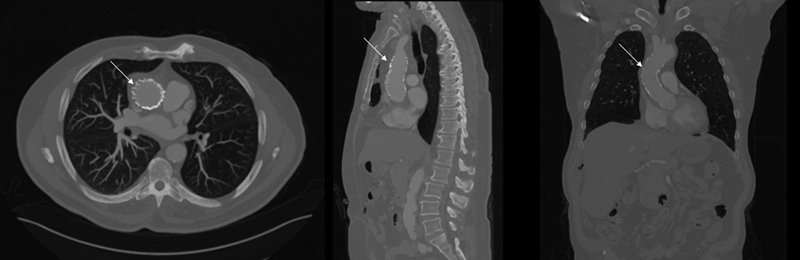

虽然开放手术是升主动脉病变的标准治疗方法,但血管内方法也是可行的选择。我们报告了一例患有 5.7 厘米升主动脉穿透性溃疡的 77 岁男性病例。考虑到患者的年龄和临床特征,他接受了 0 区胸腔内主动脉血管修补术。

Although open surgery is standard of care for ascending aortic pathology, endovascular approaches can be viable options. We report the case of a 77-year-old man with a 5.7-cm ascending aorta penetrating ulcer. Given his age and clinical profile, the patient underwent Zone 0 thoracic endovascular aortic repair.